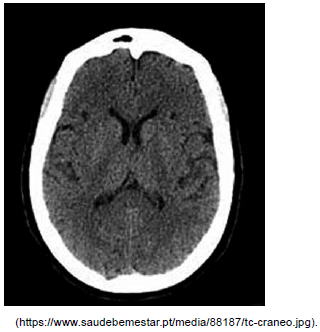

Feminina, 71 anos, hipertensa e diabética de longa data, sem controle adequado. Admitida com 45 minutos de déficit súbito. Ao exame físico: glicemia capilar de 134 mg/dL, pressão arterial de 190 x 90 mmHg, pontuação na escala do NIH de 10. A tomografia de crânio encontra-se a seguir. Assinale a alternativa correta referente ao tratamento agudo dessa paciente.